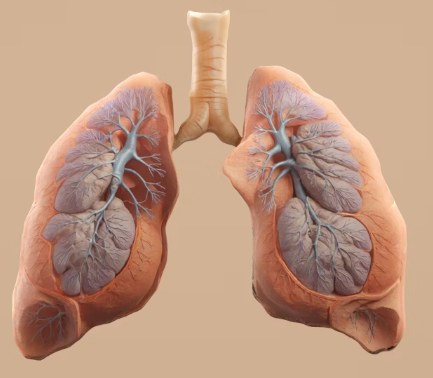

이 외에 흉부 X-ray 또는 CT를 통해 폐기종 변화나 다른 폐 질환 유무를 확인하고, 혈액 검사로 알파-1 항트립신 결핍증과 같은 특정 원인이나 합병증을 평가하기도 합니다. 의료진은 이러한 검사 결과를 종합하여 만성폐쇄성 폐질환의 진단과 중증도를 판단합니다.